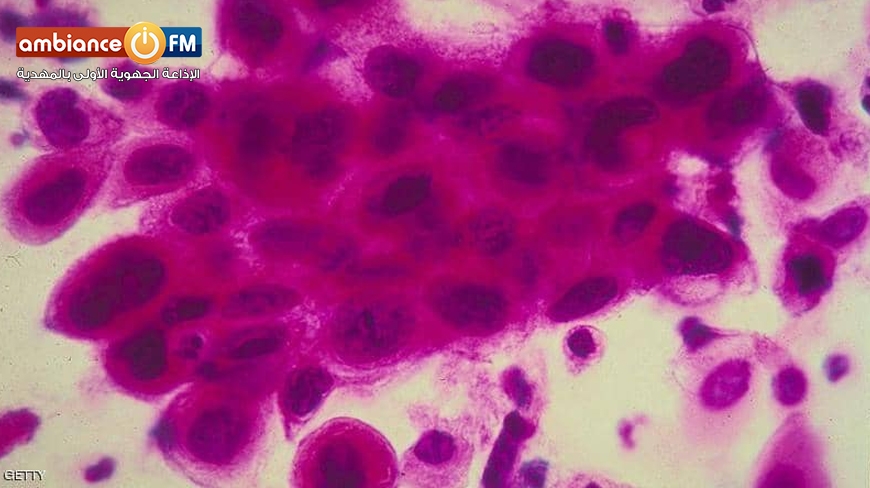

ودرس الباحثون سرطان الغدد الليمفاوية من نوع "لاهودجكينية"، وهو نوع خطير من السرطان يبدأ في العقد اللمفاوية.